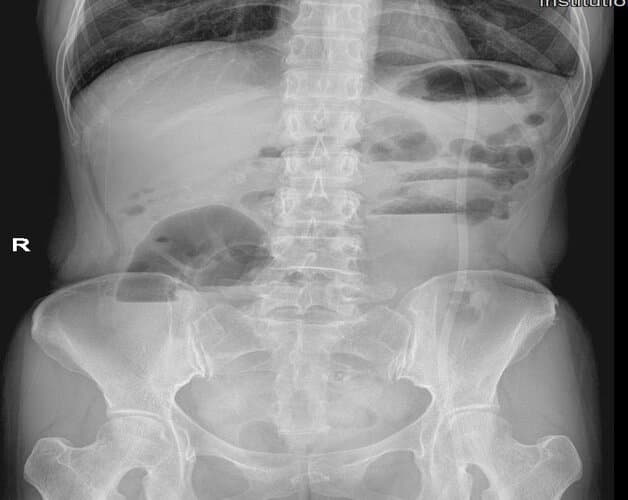

X quang ổ bụng không sửa soạn trong chẩn đoán tắc ruột

Hình ảnh nhận biết: Ruột non chướng hơi và không có hơi trong đại tràng, nhiều mức nước hơi ruột non xếp theo hình bậc thang theo chiều từ hạ sườn trái đến hố chậu phải.